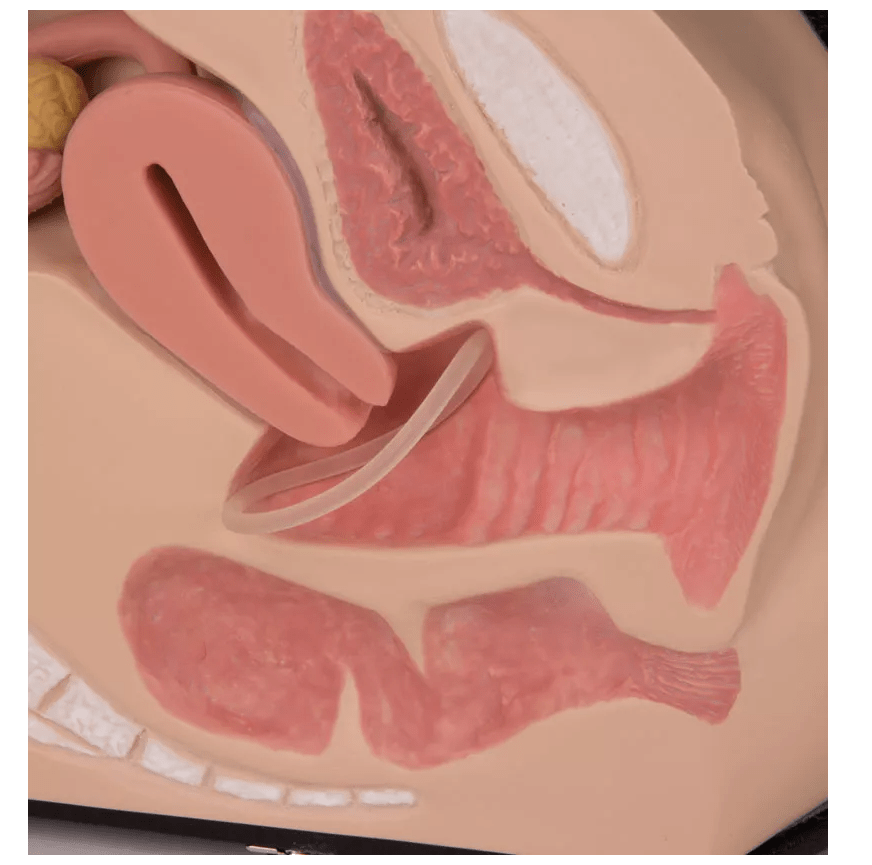

Dieses naturgetreue Anatomiemodell stellt die weiblichen Genitalorgane in Originalgröße dar und ist speziell für den Einsatz in medizinischer Ausbildung, Patientenberatung und Sexualaufklärung konzipiert. Der median geschnittene Körperabschnitt lässt sich aufklappen, wodurch die inneren Strukturen verständlich und anschaulich vermittelt werden können. Das Modell eignet sich nicht nur zur visuellen Darstellung, sondern durch das hautähnliche Material auch zur Tastuntersuchung und zur Übung medizinischer Anwendungen wie Spekulumtechnik und der Platzierung von Verhütungsmitteln.

Median geschnitten & aufklappbar zur Veranschaulichung innerer Organe

Detaillierte Darstellung von:

– kleinen und großen Schamlippen

– Scheide, Muttermund, Gebärmutterhals, Gebärmutter

– Eileitern, Eierstöcken, Harnblase, Mastdarm, Symphyse

– Kreuz- und Steißbein -